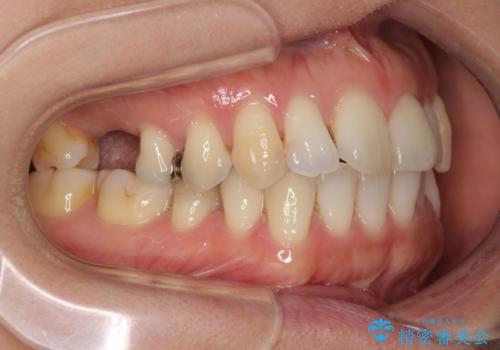

- 上下奥歯の欠損を気にして来院された患者様です。

以前矯正した後戻りにより前歯に叢生が認められたため、矯正治療の提案をしたところ、補綴治療と合わせて矯正治療を行うこととしました。

下顎欠損部はインプラントにて、上顎中間欠損部はブリッジによる補綴治療を行い、他にも気になっている銀歯をセラミックインレーやゴールドインレーにて修復治療を行うこととしました。

後戻りの程度は軽度であったため、インビザライン・ライトを用いて歯列を整えました。

再度後戻りするリスクを最小限に食い止めるため、下顎前歯の舌側を細いワイヤーで固定しました。